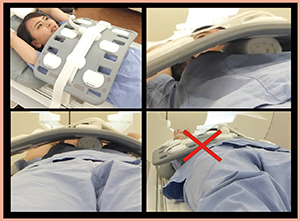

RVS用MRIは,超音波検査の体位に近い両上肢挙上でポジショニングし,体幹部コイルを用いて撮像を行っている。コイルの重みで乳房が潰れてしまうと適切にフュージョンが行えないため,コイルはタオルなどを用いて体表から浮かせて配置する必要がある(図1)。コイルを体表から浮かせるための補助具を作成してもよい(図2)。

図1 タオルを用いた場合のコイルセッティング |